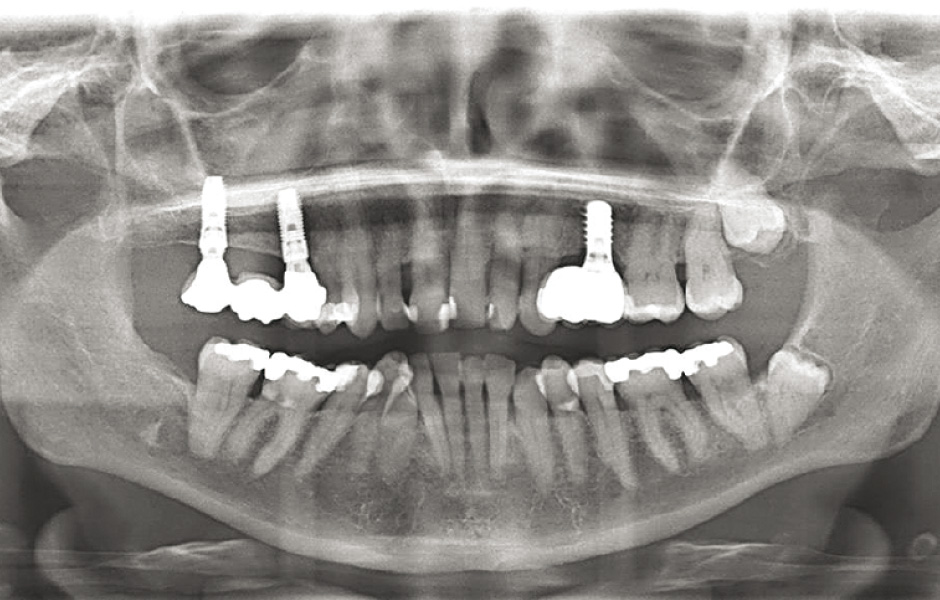

Do studie bylo zařazeno 10 pacientů s aspergilózou maxilárního sinu. U všech pacientů byl na panoramatických snímcích i na CBCT patrný radiopakní stín. CBCT navíc ukázalo, že čelistní dutina byla kompletně vyplněna homogenní patologickou masou. Chirurgická léčba sinu byla provedena za antibiotické profylaxe (Amoxicillin 2 g/den po dobu 7 dní) a intravenózní sedace (Midazolam). Kostní okénko bylo vytvořeno mikropilkou (DENTSPLY Implants), umožnilo bezpečný přístup do sinu. Po odklopení separovaného kostního fragmentu byla aspergilóza spolu s cizorodým materiálem kompletně odstraněna a dutina vypláchnuta peroxidem vodíku (H₂O₂ 3 %). Pro dodatečnou dezinfekci byla použita fotodynamická dekontaminace laserem HELBO (HELBO, Bredent Medical GmbH). Na závěr zákroku byla kostěná lamela vrácena zpět jako biologický uzávěr sinu a fixována resorbovatelnými stehy. Histopatologické vyšetření ve všech případech potvrdilo infekci aspergilózou. Po třech měsících, kdy CBCT potvrdilo nepřítomnost sinusové patologie a průchodné ostium, byla provedena augmentace kosti. Kostní bloky byly odebrány z retromolárové oblasti mandibuly a přeneseny ve 3D konfiguraci podle split-bone block techniky v kombinaci se sinus liftem. Sinus byl augmentován autologní kostí a biomateriálem (FRIOS Algipore®, DENTSPLY Implants) vrstvenou technikou. Po dalších třech měsících byly do augmentované oblasti zavedeny implantáty. O další tři měsíce později byly implantáty odhaleny a následně byla zhotovena definitivní protetická náhrada.“

Obr. 1: CBCT: radiopakní stín v levém maxilárním sinu.